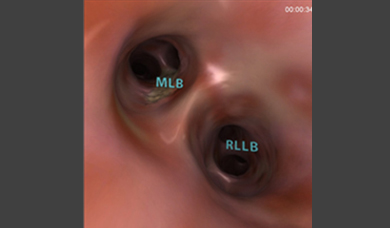

It provides a comprehensive solution for flexible bronchoscopy training of pulmonary and critical care physicians, thoracic surgeons, anesthesiologists, interventional pulmonologists and others. Fundamental skill tasks and complete clinical procedures provide an optimal learning environment for motor, cognitive and coordinative skills acquisition, as well as diagnostic and therapeutic clinical hands-on experience towards competency.

- Realistic and comprehensive bronchoscopic simulation training away from patient, designed to support both team and solo training sessions

- Didactic environment enhancing the learning curve, including skill-targeted tasks, procedural tasks, aided/un-aded clinical cases – each followed by comprehensive performance feedback

The simulator demonstrated validity in differentiating skill in scope manipulation and airway anatomy, but did not discriminate skill levels in anatomic orientation or identification of lymph nodes. Bronchoscopy simulation was viewed as helpful by all levels and should be considered before performance on patients.